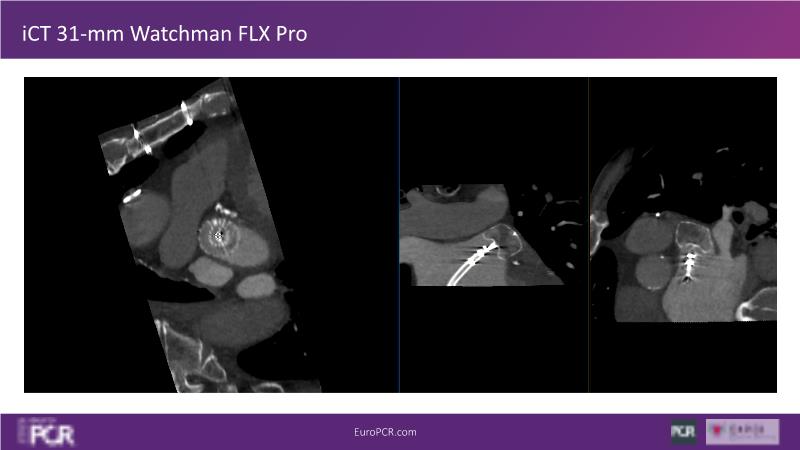

Explore this session to discover the latest innovations in interventional cardiology images, including the benefits of artificial intelligence and angio-CT in PCI/SHD procedures. Learn about Alphenix Evolve and the initial experiences with AI imaging in daily cathlab practice, alongside intraprocedural angio-CT guided LAAO, and engage in discussions on meaningful tools that can transform patient care.